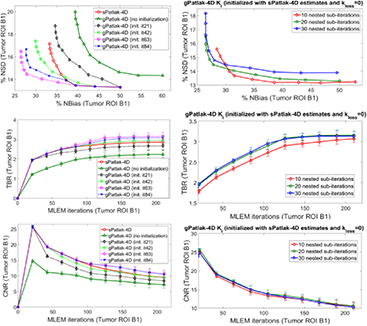

Nevertheless, non-linear 4D reconstruction methods involve more complex objective functions, and a more advanced initialization scheme may be helpful. In particular, gPatlak 4D algorithms involve non-linear parameters, and thus, their EM convergence is sensitive to initialization. Therefore, for gPatlak 4D nested algorithm we evaluated (i) a conventional scheme involving initialization of Ki and V estimates with unity values, and (ii) a novel sPatlak-based scheme, where Ki and V parameters were initialized with respective sPatlak 4D estimates. In both cases, kloss initial value was set to zero, which is equivalent to the sPatlak method. Although initialization with zero values is not recommended in ML-EM algorithms to avoid trapping of estimates to zeroes in subsequent iterations due to the multiplicative update mechanism, kloss belongs to an exponential term in the gPatlak model and thus zero is effectively translated as the unity value. The number of sPatlak ML-EM iterations employed to produce the parameter values for gPatlak initialization were determined based on noise-bias trade-off performance in simulated data.

3.1.4. Conventional versus nested Patlak 4D ML-EM and number of nested sub-iterations.

The expected gain in ML-EM convergence rate for the nested relative to the conventional, i.e. non-nested, 4D sPatlak implementations was illustrated qualitatively and quantitatively in figures 5(b) and (c) respectively. In particular, visual inspection of B1 and B2 lesions contrast as a function of the iteration cycles in simulated Ki images of figure 5(b) suggested a faster contrast recovery, and thus convergence rate, for the nested sPatlak Ki images. In addition, the respective noise-bias curves in figure 5(c) indicated smaller bias values at matched noise levels for the nested sPatlak 4D implementation.

Moreover, a mildly faster 4D ML-EM convergence was recorded as the number of nested sub-iterations increased per global iteration step. This is conjectured from all three plots of the 2nd column of figure 7. However, the gain in bias and TBR contrast became progressively negligible when more than 20 sub-iterations were involved, as convergence had already been established at earlier iterations in these cases. Meanwhile, the noise was being steadily deteriorated in the same cases, due to the higher number of nested updates involved per global iteration step. As a result, for higher than 20 nested sub-iterations, image noise kept increasing relatively faster than TBR lesion contrast and, consequently, CNR started dropping at later iterations. Although not included in the results, it should be noted that a very small number of sub-iterations (<10) resulted in consistently slower convergence in all nested 4D algorithms.

Figure 7. Ki noise-bias trade-off, TBR and CNR quantitative analysis over 20 noise realizations for simulated B1 ROI for different initialization schemes (1st column) and number of nested ML-EM Patlak sub-iterations (2nd column) for a range of conventional and novel 4D-Patlak methods. The sPatlak-4D and the first gPatlak-4D method (red and green curves at 1st column) were initialized with the conventional method (Ki = 1, kloss = 0, V = 1). All methods in 1st column utilized 20 sub-iterations. Finally, all gPatlak-4D methods of 2nd column were initialized with kloss = 0 and Ki and V values estimated from 63 sPatlak MLEM iterations.

The noise-free images in figure 5(a) demonstrate that the (s/g)Patlak 4D ML-EM algorithms converge in theory to the global optimal solution regardless of the initialization method. Thus, our findings indicated proper theoretical EM convergence properties for the implemented algorithms. In the presence of noise, however, the conventional method of initializing 4D ML-EM with Ki = 1, kloss = 0 and V = 1 parameter values, yielded correct EM convergence only in the case of 4D sPatlak method, as it can be conjectured by comparing 3rd and 4th row in figure 5(b). Nevertheless, as the Ki images of the last 2 rows in figure 5(b) illustrate, higher Ki lesion contrasts were attained with 4D gPatlak, compared to sPatlak (3rd row), after initializing the gPatlak 4D method with Ki and V estimates from the first 21 (5th row) or 3 × 21 = 63 (6th row) sPatlak iterations.

The importance of sPatlak-based initialization for gPatlak 4D algorithms was further demonstrated by the noted bias reduction as well as TBR and CNR score enhancements in figure 7 (1st column plots), when more sPatlak 4D global iterations were involved in the initialization of gPatlak 4D algorithm. However, after 3 cycles of 21 sPatlak ML-EM initial iterations, no additional benefit was observed for gPatlak 4D EM convergence rate. Thus, under noisy conditions, gPatlak 4D reconstruction may require a minimum number of sPatlak 4D iterations for its initialization, to ensure proper convergence and thus high quantification accuracy in Ki reconstructed images.

3.2.4. Clinical impact of number of nested sub-iterations and gPatlak initialization.

The series of WB Ki images in figure 9 illustrate the convergence of sPatlak and gPatlak 4D methods, when applied to the same patient dataset and after being initialized with the proposed schemes. The two 4D algorithms converged to different but similar sPatlak and gPatlak solutions in the last two cycles of 21 iterations.

Moreover, the TBR and CNR plots describe the quantitative effect on 2 chest ROIs of the number of nested ML-EM sub-iterations as well as that of sPatlak-based initialization for gPatlak 4D algorithm. In particular, the plots of the 2nd row suggested superior TBR and CNR performance for both ROIs in clinical gPatlak-4D Ki images, when at least 3 × 21 ML-EM sPatlak iterations are employed for its initialization. Any higher number of iterations only resulted in negligible convergence acceleration. Furthermore, the TBR and CNR scores of the 3rd row suggested a minimum number of 20 nested ML-EM sub-iterations to sufficiently accelerate convergence without increasing noise in the Ki images.